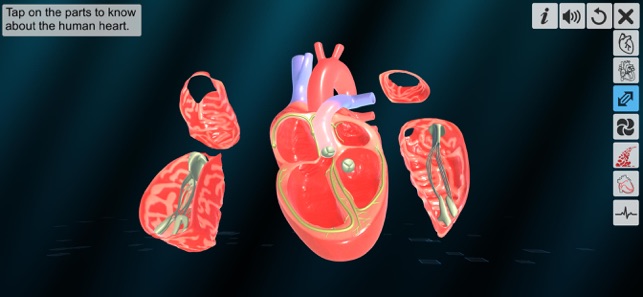

3. Explode of chambers.

‘Heart - An incredible pump’ app explains the external and internal structure of human heart through the simulation 3D model to improve the comprehension of the topic. The user can interact with the 3D model by tapping the model and getting acquainted with the particular part of the human heart. Tapping the model displays the name of the part and also the simulation module is appropriately supported with in depth information about each external and internal structure part.